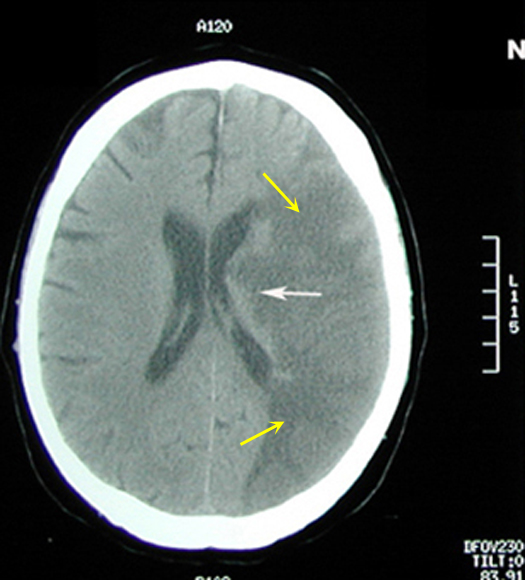

Figure 1: Non-contrast axial CT brain

|

Acute to Subacute Infarct

Case 1:

Imaging findings: Figure 1

- Large area of low CT attenuation (hypodense) is seen involving the left middle cerebral artery distribution (yellow arrows), with involvement of both gray and white matter.

- White arrows points to involvement of basal ganglia region with infarction also.

- Gyri and sulci are effaced on the left side (compare to normal right side).

|